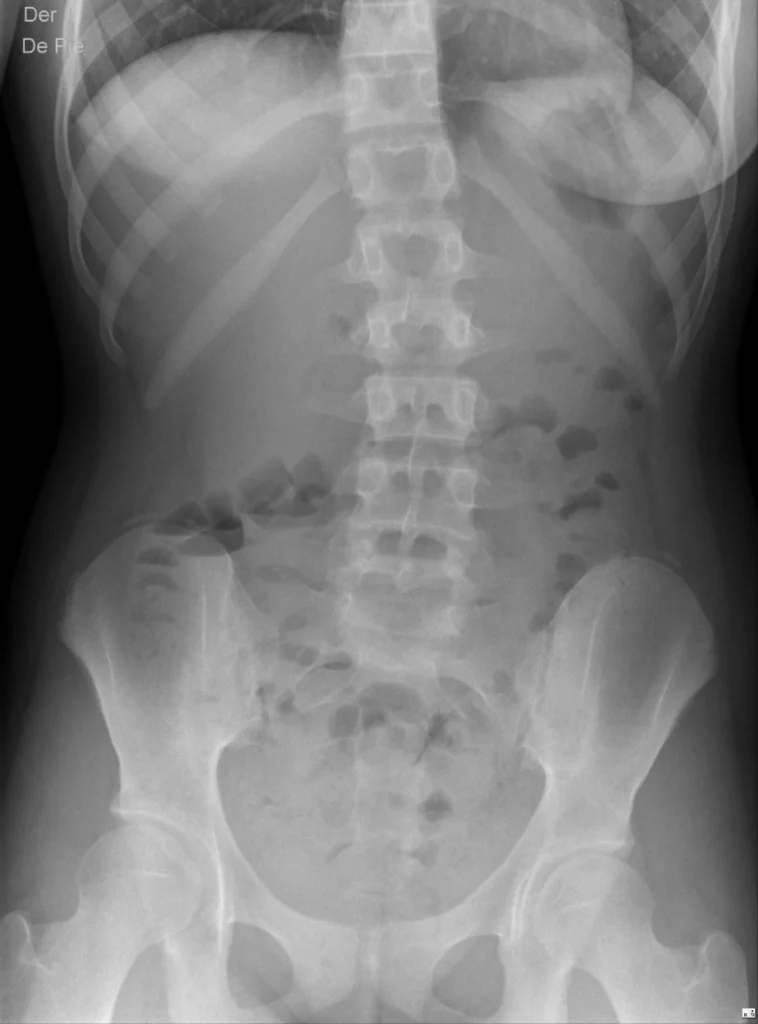

Radiografía de abdomen anteroposterior en decúbito supino

Radiografía simple de abdomen obtenida con el paciente en bipedestación y proyección anteroposterior. Se visualiza el abdomen completo, incluyendo el diafragma y la pelvis, lo que permite evaluar la distribución del gas intestinal, la presencia de aire subdiafragmático (signo de neumoperitoneo) niveles hidroaéreos.

“Radiografía de abdomen, anteroposterior en bipedestación”

En orden de mención:

- Radiografía: método diagnóstico

- Abdomen: región anatómica evaluada

- Anteroposterior: proyección del haz de rayos X

- En bipedestación: posición del paciente durante la adquisición